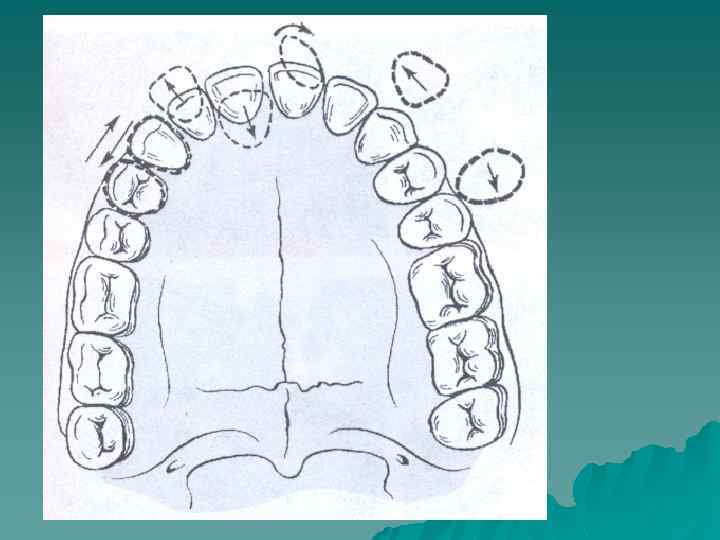

Зубы могут занимать неправильное положение в пределах зубного ряда или располагаться вне его. Соответственно трем взаимно перпендикулярным направлениям выделяют шесть основных видов неправильного положения зубов четыре в горизонтальном и два - в вертикальном направлениях.

Соответственно различают u вестибулярное u оральное u дистальное u мезиальное положение зубов u супраположение u инфраположение, u тортоаномалию u транспозицию зубов